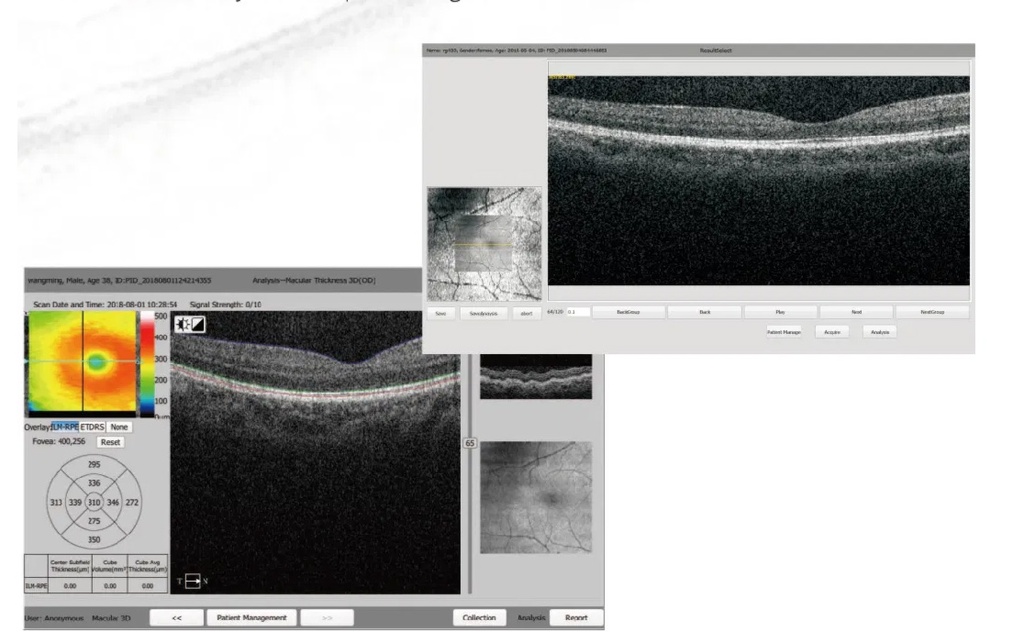

0911 OCT

Methodology: Spectral domain OCT

Axial resolution: ≤ 6 µm (in tissue)

Transverse resolution: ≤ 20 µm (in tissue)

Scan depth: ≥ 2.5 mm (in air)

Scan range: ≥ 6 mm

Scan speed: ≥ 24,000 A-scans/sec, up to 36,000 A-scans/sec

Scan modes: 30, Raster, Circle

Fundus image: OCT en face

Focus adjustment: -150 to +150

Pupil diameter: ≥ 3 mm

OCT light source: 840 nm SLD

Optical power: 750 µW (at cornea)

Operation: 13.3''touch screen, optional external mouse or keyboard

Power supply: 100-240 V, 50/60 Hz

Dimensions: 497 mm × 395 mm × 490 mm (L× W × H)

Weight: 34 kg (75 lbs)

Fixation target: External fixtion